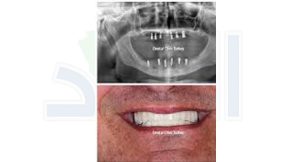

زراعة أسنان من جسد المريض نفسه لأول مرة في التاريخ